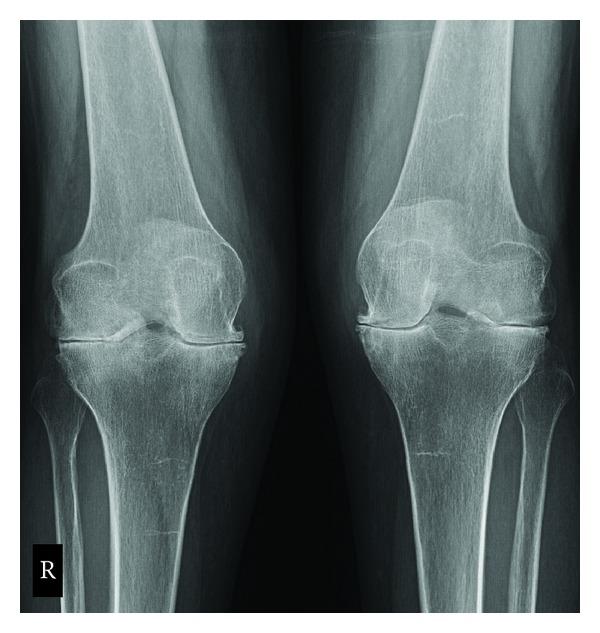

The definitive treatment for advanced joint destruction in the late stages of rheumatoid arthritis can be successfully treated with total joint arthroplasty. Total knee arthroplasty has been shown to be a well-proven modality that can provide pain relief and restoration of mobility for those with debilitating knee arthritis. It is important for rheumatologists and orthopedic surgeons alike to share an understanding of the special considerations that must be addressed in this unique population of patients to ensure success in the immediate perioperative and postoperative periods including specific modalities to maximize success.

类风湿关节炎晚期严重关节破坏的最终治疗方法是全关节置换术,该方法已被证明是一种行之有效的治疗方式,能为患有严重膝关节炎的患者缓解疼痛并恢复活动能力。对于风湿病学家和骨科医生而言,共同理解在这类特殊患者群体中必须考虑的特殊因素非常重要,以确保在围手术期和术后短期内获得成功,这包括采用特定方式来实现最大程度的成功。